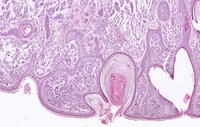

384. Hautkrebs: Algorithmus kann den Pathologen bei der Diagnose unterstützen

Künstliche Intelligenz gewinnt in der Medizin zunehmend an Bedeutung: Maschinen werden mit Informationen gefüttert und trainieren so einen Algorithmus, um große Datenmengen und medizinische Bilder zu